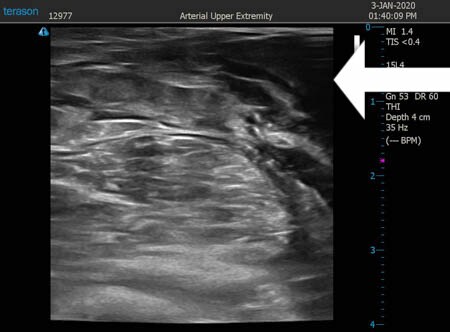

いつものように3Dタッチビュー(超音波)で

皮下脂肪層を評価してみましょう。

右ふくらはぎ

↓ ↓ ↓